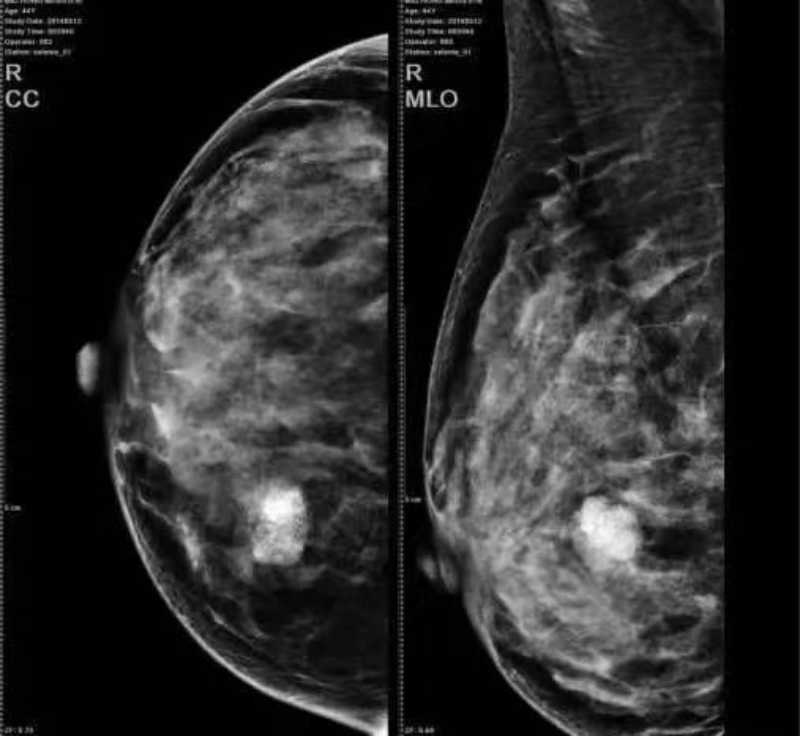

日前,我院放射醫學科引進全數字化乳腺鎢靶機, 該設備能安全有效地應用于乳腺癌篩查和診斷,對比以往的傳統乳腺數字X線攝影,這款新設備還可以進行乳腺的斷層攝影,顯著提高病灶的檢出率和準確率。

傳統的數字乳腺X線攝影是二維圖像,對于非鈣化病變很可能重疊在正常乳腺組織內,病變就顯示不清,甚至不能看到,乳腺三維斷層合成成像就是球管在轉動的同時在不同的角度進行拍攝,通過后處理,我們可以得到類似CT的重建圖像,把乳腺分割成1mm一層,分成無數層,有效的去除了組織重疊。對于腫塊及其邊緣的顯示明顯優于傳統數字X線檢查,特別是對于結構扭曲的檢出率明顯高于傳統乳腺數字X線攝影。

同時影像更清晰直觀、定位更準確、照射范圍全面,對早期乳腺癌微鈣化敏感較高、顯示清晰,可發現小于5mm的癌腫。在良、惡性腫瘤的鑒別診斷方面具有明顯優勢,尤其對微鈣化的檢測更是其他設備無法替代的,其確診率達到80-90%。